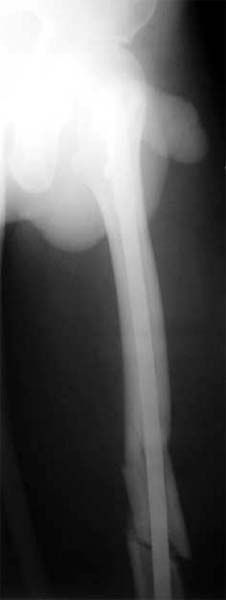

股骨多段粉碎骨折 采用闭合穿钉法,带锁髓内钉内固定